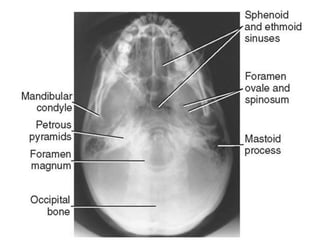

Submento-Vertical VIEW. (SMV)/Basilar view.

• The patient faces the x-ray tube, with the chin and neck

hyper-extended.

• If the patient is supine, the table is lowered gently and

angled until the base line is parallel with the tube.

• If the patient is sitting, the neck is hyper-extended as far

as possible and the table is then angled until the RBL is

parallel with it.

• Centre; In the mid-line between the angled of the jaw,

with the tube angled 5° towards the face.